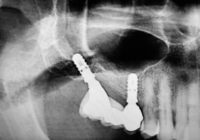

La stampa 3D come ausilio diagnostico nella gestione del mascellare superiore atrofico

La stampa 3D è una tecnologia di fabbricazione additiva che consente di realizzare un oggetto tridimensionale partendo da dati informatici e viene utilizzata in molti campi: dall’industria, all’arte e in medicina. Attualmente, grazie alle stampanti 3D, abbiamo la possibilità di ricostruire fisicamente le strutture anatomiche visibili nelle immagini radiologiche. Leggi »